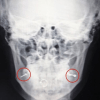

Всего просмотров: 16202  20 января 2021В Люберцах врачи экстренно прооперировали пациентку с неправильным пирсингомВрачи Люберецкой областной больницы провели пациентке операцию по удалению пирсинга с пластикой местными тканями, сейчас девушка выписана под амбулаторное наблюдение врача стоматолога-хирурга, сообщили в медучреждении. ⠀

20 января 2021В Люберцах врачи экстренно прооперировали пациентку с неправильным пирсингомВрачи Люберецкой областной больницы провели пациентке операцию по удалению пирсинга с пластикой местными тканями, сейчас девушка выписана под амбулаторное наблюдение врача стоматолога-хирурга, сообщили в медучреждении. ⠀